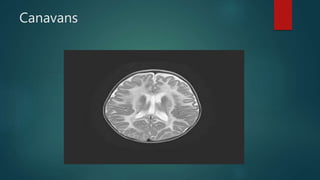

Canavans

• #51 MRI confirms the megalencephalic appearance and provides more detail of the white matter disease, which is typically diffuse, bilateral, and involving the subcortical U-fibres